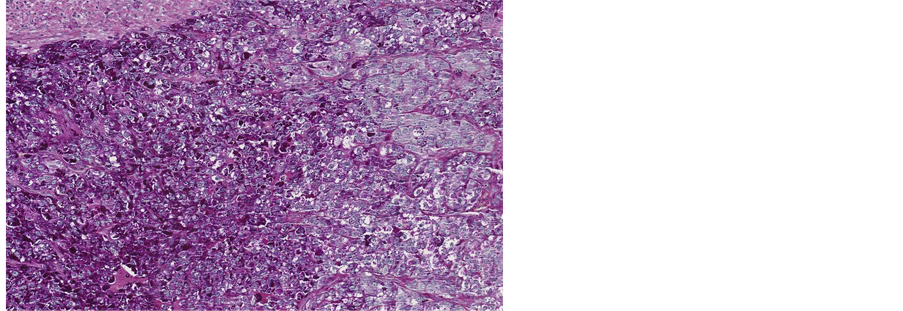

The Periodic acid-Schiff (PAS) staining for glycogen was positive (Figure 3), and Periodic acid-Schiff-diastase (PAS-D) staining for mucus was negative (Figure 4).

Figure 3. Microscopic appearance of the endometrial tissue from curetting specimen-clear cell carcinoma, Periodic Acid- Schiff (PAS) staining, ×10.